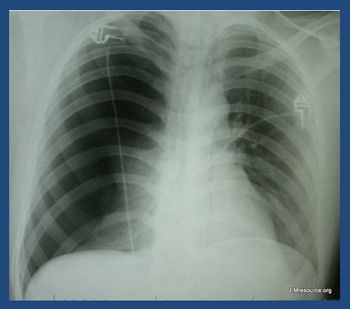

The patient reports the chest pain began 6 days ago during a vacation abroad. She denies any injury. What does the chest x-ray reveal?